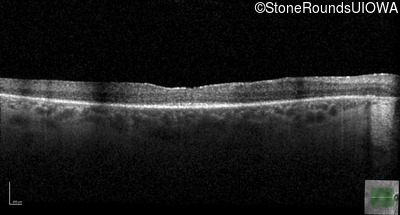

Age at visit:

36 years

OD

OS

20/32 -2

20/40 +2

AR Retinitis Pigmentosa

ZNF408

His455Tyr CAT>TAT

Arg567Stop CGA>TGA

AR